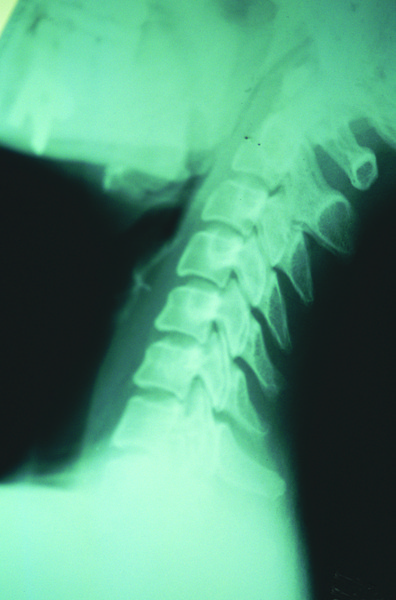

목디스크

목디스크는 목 부근의 척추인 경추와 경추 사이에 위치한 추간판(디스크)가 손상되어 추간판의 수핵이 척추신경을 압박하거나

접촉부에서 염증을 발생시킴으로 발생하는 질환입니다.

거북목, 일자목 (일자목증후군)

거북목,일자목은 C자형의 곡선을 유지해야 할 목뼈의 배열이 일자처럼 직선으로 변형된 것으로 ‘경추의 직선화’ 라고도 불리는 질환입니다.

“경추는 목뼈를 말하며 움직임이 큰 편이기 때문에 손상을 받기 쉬우며 평소 운동량도 많기 때문에

관절이 악화되거나 추간판이 돌출되는 경우 등 다양한 문제를 일으킬 수 있습니다.